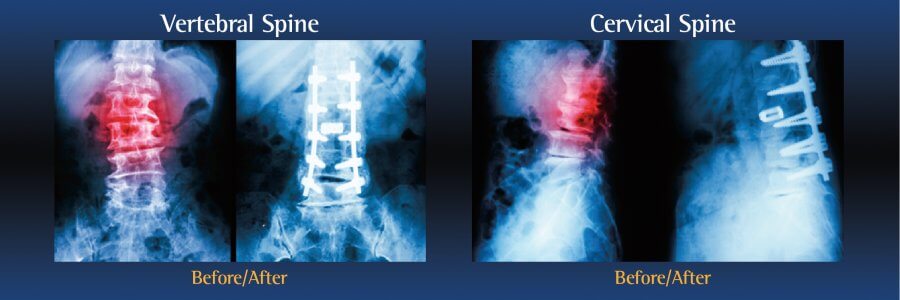

Types of spinal fusion surgery

There are several types of spinal fusion surgery. The type of procedure performed will depend on the patient’s individual condition, as well as the location of the pain:

- Cervical Fusion is performed on the neck

- Lumbar Fusion is performed on the lower back

During the operation, an incision is made in the neck, back or abdomen. Bone, debris, bone growths, lamina, and/or the damaged vertebral disc may be cleared from the spine, creating more space and relieving pressure on the spinal nerves. The surgeon will then take the proper steps to correct the patient’s specific problem.

Bone grafts may then be placed in the space or along the side of the spine. If additional support is needed, metal hardware (including pins or screws), may be used to steady the spine as it fuses. The incision is closed to finalize the surgery.

The grafts will grow into solid bone, fusing together the vertebrae. Patients may have to wear a back brace post-surgery, which will support your spine and keep the vertebrae from moving as the grafts fuse together.